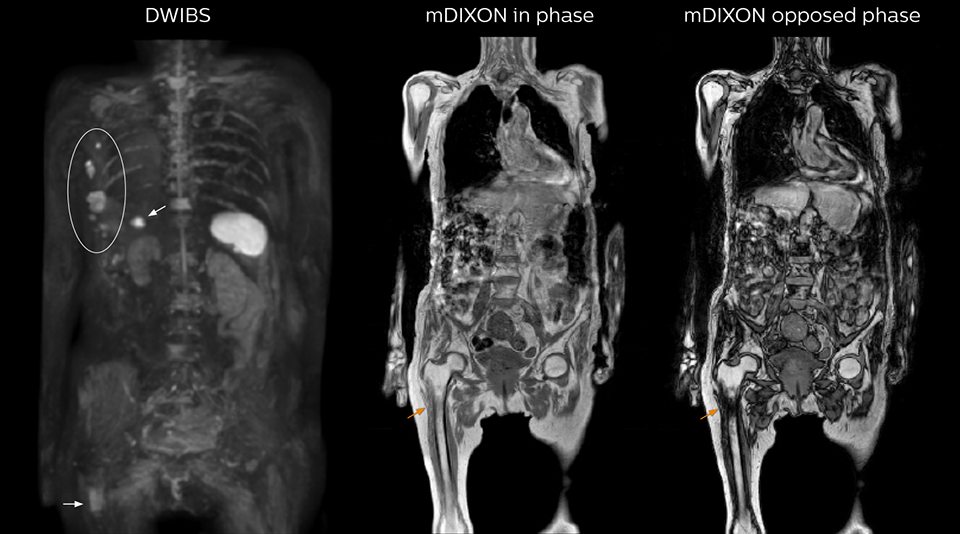

“When we limited the scan coverage to the area from neck to femur, we could fit more clinical information in approximately the same scan time. So, we added coronal mDIXON, sagittal T1-weighted, and sagittal STIR sequences to our examination, instead of performing only axial DWIBS and coronal single-shot TSE scans.”

The single shot T2-weighted TSE images are used for morphology and compared to DWIBS images to identify T2 shine-through. Sagittal STIR images are used in patients with inflammation or bone metastasis.

Coronal DWIBS is faster and improves image quality

“Switching to coronal DWIBS – rather than axial – further shortens scan time,” says Mr. Naka. “Important is that a dS SENSE factor of 5 shortens exam time while high image quality can be maintained, thanks to Ingenia’s dStream architecture.” He adds that the coronal orientation also avoids artifacts that are specific to combining axial images.

Kawasaki Sawai Hospital’s whole body protocol also includes an mDIXON FFE sequence. Because mDIXON provides images for four contrast types – water only, fat only, in-phase and out-of-phase – from a single acquisition, it is useful in many ways.

“mDIXON FFE allows us to quickly get information we need to assess the presence of fat. That gives us more information when we need to diagnose bone lesions, and when we are asked to judge fat-containing lesions such as hepatocellular or renal carcinoma,” Dr. Nobusawa says.

“The mDIXON fat images can help us to differentiate fatty bone marrow from bone lesions. This is especially useful in elderly people, who tend to have fattier bone marrow. The water images provide a high signal-to-noise ratio in the intestinal canal, which is valuable for visualizing lesions in the colon,” he says.

“In-phase and out-phase sagittal T1-weighted FFE images help us to visualize and further characterize bone lesions such as metastasis and bone-marrow hyperplasia that have high signal on DWI. These images are also used throughout radiotherapy, to monitor changes in the fatty bone marrow.”